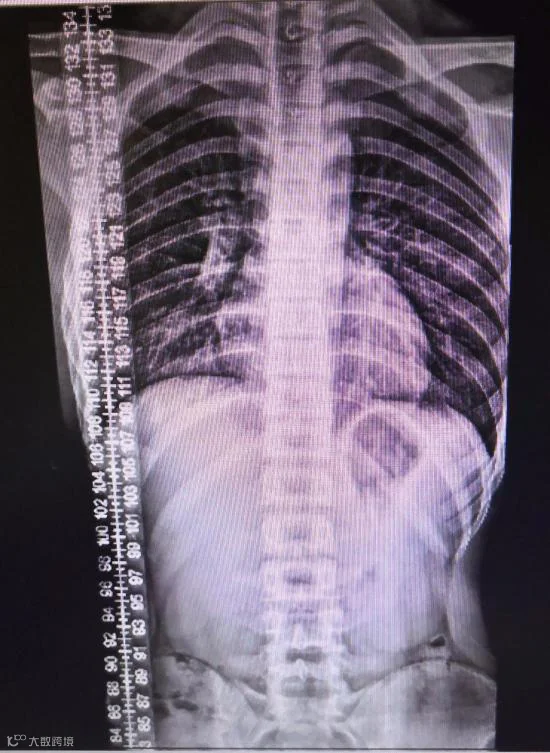

15岁少年脊柱侧弯

“脊柱侧弯,又称脊柱侧凸,是指脊柱的某一节段偏离身体中线向侧方弯曲。许多人的脊柱都有一些弯曲,但少数人会出现大幅度脊柱弯曲,呈 S 或 C 形。如果这种弯曲程度很大,则会导致腰背疼痛甚至呼吸困难。”

“许多脊柱侧弯的成人患者前来就诊的原因往往是背部疼痛。这类患者可能从十几岁就患上这种疾病,随着年龄的增长,脊柱弯曲程度逐渐加重,脊柱附近的神经也因此受到压迫,不仅引起背部疼痛,也会引起肢体无力和麻木等症状。”